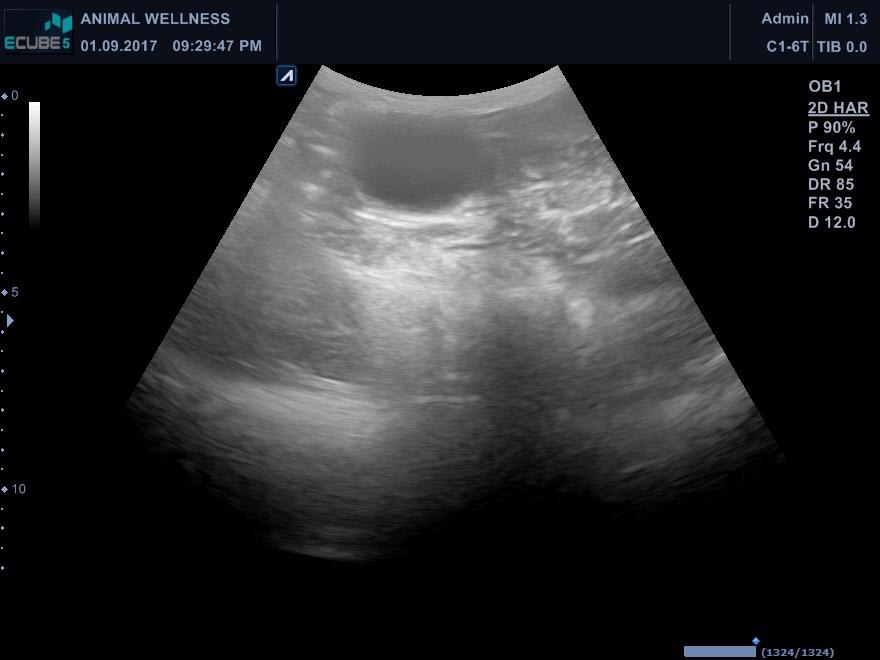

Vet said there's slight inflammation of Maicah's heart, stomach is pushed up -possible pyometra based on her history. See latest xray + old 1/17 sonogram pic attached. Waiting for head vet's feedback based on this am's ultrasound. Maicah is 10-12yo, had 2 CSections- prev. vet did not spay on her last csection, said her uterus was damaged (from prev pregnancies before i adopted her) & there was adhesion so it's risky. How can we get an accurate diagnosis? Is operation still a good option? Thanks!

Unfortunately, the x-rays are not showing up as well here as the originals would, so I'll comment on what I see, but I could easily be missing something. The heart does not appear enlarged, but their are some distended arteries in the x-ray that make me suspicious of heart disease and more specifically heartworm. The abdomen is generally distended and the liver appears somewhat enlarged. This can happen with the heart disease I mentioned or some other condition affecting the liver. I do not see an obvious pyometra on the x-rays or ultrasound (sonogram). I wish I could help you with the other questions, but it's impossible without me knowing the cat's full history, or having the opportunity to examine the cat myself. One thing we can offer on Petco Pet Education Center, formerly Petcoach is a consultation. This is a service that you would have to pay for, but it would allow you to text back-and-forth with one of our experts and send as many pictures as you want. With these consultations, we can help to identify the problems by gaining all the necessary information. Otherwise, you may seek a second opinion from another veterinarian in your area. I hope this is somewhat helpful and everything turns out OK Maicah.